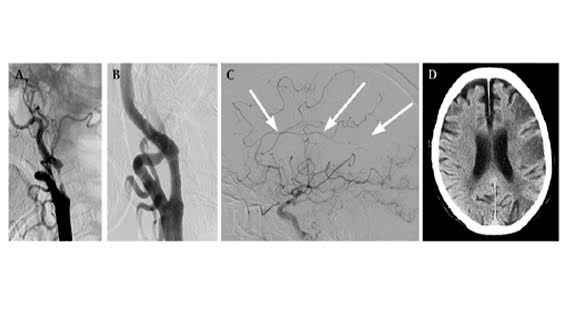

BN đến khám tại Bệnh viện Quân y 103, được xác định hội chứng tiền đình trung ương. Truy tìm nguyên nhân, siêu âm động mạch cảnh phát hiện hẹp gần hoàn toàn động mạch cảnh trong trái. Chụp cộng hưởng từ mạch thấy mất dòng chảy động mạch cảnh trong bên trái, có nhồi máu nhỏ trong não chưa dẫn tới liệt chi.

Ca hẹp động mạch cảnh trong ngoài sọ bên trái gây nhồi máu não.

Chụp cộng hưởng từ mạch máu (MRA) hoặc chụp CT đa lớp cắt (MSCT) để đánh giá toàn thể hệ thống động mạch trong và ngoài sọ. Phương pháp chụp mạch số hóa xóa nền (DSA) sọ não thường sử dụng trong can thiệp điều trị. Đây là phương pháp đưa ra chẩn đoán chính xác nhất về tình trạng lòng mạch, được coi là tiêu chuẩn vàng trong chẩn đoán bệnh mạch máu.